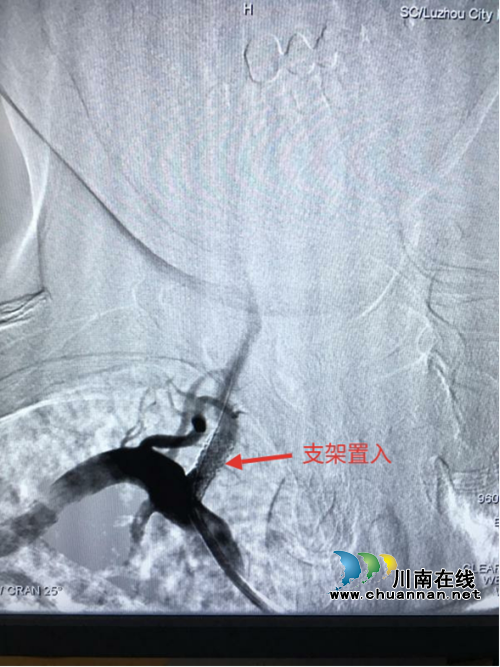

经过精心准备,9月27日,手术如期进行。医生们首先进行脑血管造影,了解狭窄血管的情况,制定手术方案。造影提示:右侧椎动脉起始部位狭窄率约85%。经过准确测量,选用5.0×15mm的椎动脉支架,经过导引导丝的引导,准确将支架置入狭窄血管处,经过扩张、释放,支架准确的将狭窄血管打开,造影显示血流恢复。手术历时1小时左右顺利结束。

支架置入后